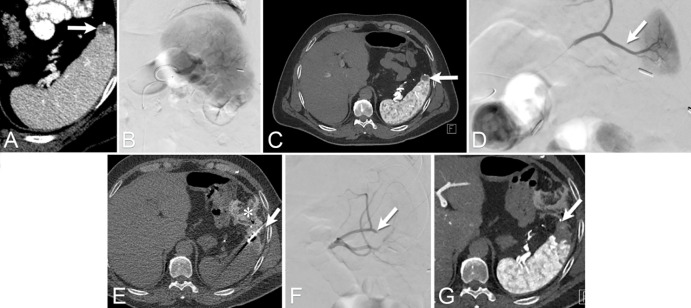

Figure 7:

Images from combination of transarterial chemoembolization (TACE) and ablation using an angio-CT system in a 58-year-old woman presenting with a 2.7-cm solitary hepatocellular carcinoma on the left hepatic lobe. (A) Image from digital subtraction angiography performed at the level of A4 artery demonstrates tumor blush (arrow). (B) CT scan during hepatic arteriography at the level of the common hepatic artery demonstrates hypervascular tumor at the segment IV (arrow). (C) Image from percutaneous ablation under CT guidance performed with two microwave antennas. Following the ablation, TACE was carried out to address any potential residual tumor areas due to heat-sink effect adjacent to the paraumbilical vein. (D) Immediate intraprocedure intravenous CT scan shows successful chemoembolization and ablation of the target tumor (arrow). Note patent paraumbilical vein (*). (E) CT scan 6 months after the ablation helps confirm successful procedure with lacelike arterial enhancement at the treated tumor (circle).

Figure 10:

Images from combination transarterial embolization (TAE) and cryoablation for renal cell carcinoma (RCC) using angio-CT in a 90-year-old man presenting with symptoms suggestive of RCC. (A) Contrast-enhanced CT scan shows a 4.3-cm solid enhancing mass in the upper pole of the left kidney, suggestive of RCC. Given the lesion’s size, a combination TAE and cryoablation procedure was performed. (B) TAE using a lipiodol-ethanol mixture was performed under fluoroscopic guidance followed immediately by (C, D) percutaneous cryoablation. Note that the residual contrast staining from the embolization allowed for clear visualization of the target lesion during the ablation.